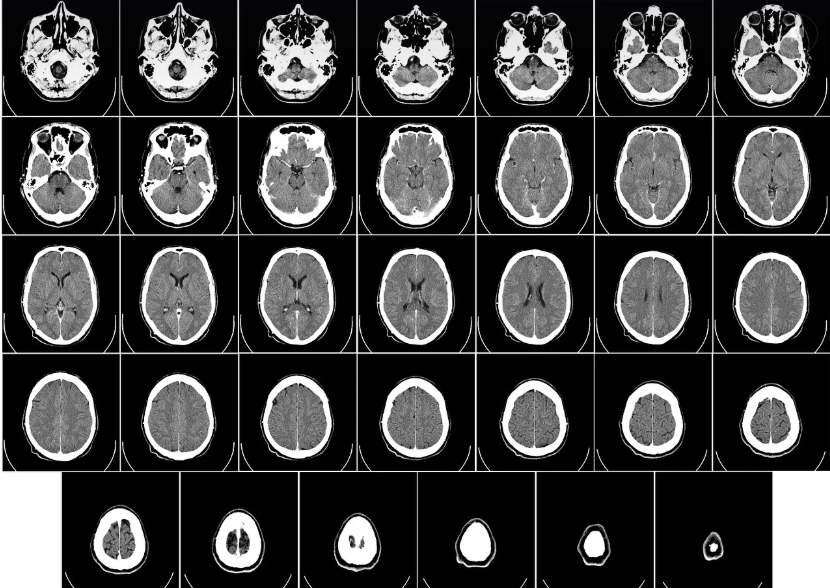

CT(Computed Tomography)는 X-ray를 다양한 각도에서 촬영한 뒤, 컴퓨터로 영상을 재구성해 인체의 단면 이미지를 얻는 검사 방법입니다. 일반 X-ray보다 훨씬 더 정밀하게 내부 장기와 조직을 확인할 수 있어, 종양, 출혈, 장기 손상, 골절 등 다양한 질환의 진단에 사용됩니다.

CT검사 과정은 어떻게 이루어지나요?

검사 전, 환자는 금속 물질(목걸이, 시계 등)을 제거하고, 경우에 따라 조영제를 정맥주사로 투여받습니다. 조영제는 혈관이나 장기 구조를 더 뚜렷하게 보이게 도와줍니다. 검사대에 누운 뒤, 원형 기계(가나트) 안을 통과하며 몇 분간 촬영이 진행됩니다. 대부분의 경우 검사 시간은 5~10분 정도입니다.

일반 X-ray는 2차원 평면 이미지만 제공하는 반면, CT는 단면 영상을 통해 더 입체적이고 정확한 정보를 제공합니다. 특히, 복잡한 구조의 장기나 조직을 분석할 때는 CT가 훨씬 유리합니다.